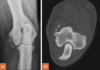

90 day labrador, CT at level of semilunar / trochlear notch. Is this normal or delayed?

Should be fused by 10 weeks (70 days), but lit says considered delayed/incomplete if the lucency is visible after 100 days.

Incomplete ossification imaging description

l radiolucent line up to 1 mm wide, extending proximally from the trochlear articular sur face to the physeal scar or supratrochlear foramen (50% cases)